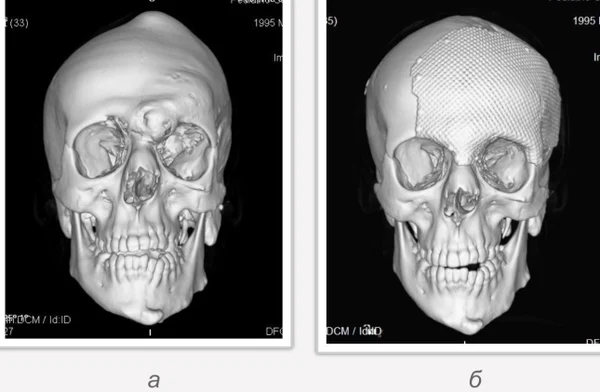

Удаление опухолей черепаВ качестве примера лечения пациентов с опухолями черепа привожу личное наблюдение пациента грудного возраста с опухолью черепа. В возрасте 1 мес. у ребёнка в затылочной области слева родителями обнаружено плотное образование диаметром 5 мм. За 3 мес. до госпитализации образование значительно увеличилось в размерах. При поступлении в возрасте 6 мес. в затылочной области слева (в проекции лямбдовидного шва) имеется безболезненное, плотное, неподвижное, бугристое образование размерами 5 х 4 х 2 см. При КТ и МРТ головы выявлена опухоль черепа в области астериона слева, обладающая преимущественно интракраниальным ростом (рис. 30 а). Ребёнку выполнено удаление опухоли черепа (рис. 30 б). Образовавшийся дефект черепа больших размеров закрыт перфорированной титановой пластиной (рис. 30 в). При наблюдении пациента в течении 2-х лет рецидива заболевания и деформации черепа не отмечалось.